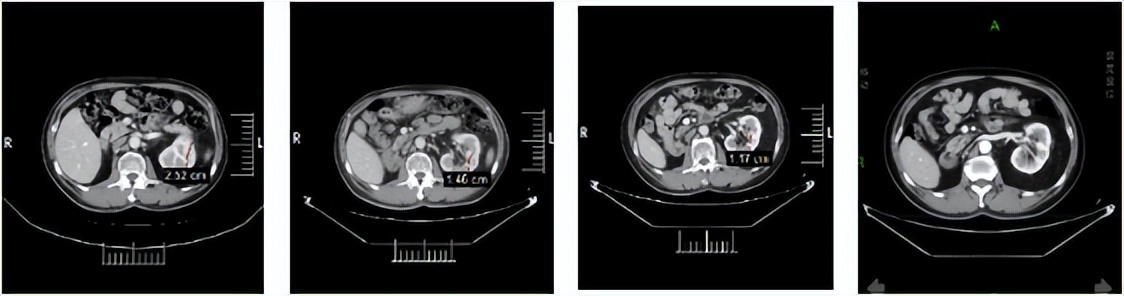

2024年1月3日:治疗4个月后,首次达到PR。

2024年5月9日,决定永久停用信迪利单抗,下调一个剂量水平(4mg,po,qd,D1-14,q3w)恢复呋喹替尼治疗。自此,截至2026年3月30日,呋喹替尼单药治疗约2年且仍在维持中。2026年3月12日行最近一次疗效评估仍处于PR,PFS已达30.4个月。

靶病灶T01:左肾下极

靶病灶T02:左肾上极

靶病灶T03:左侧肾上腺

靶病灶T04:左侧竖脊肌